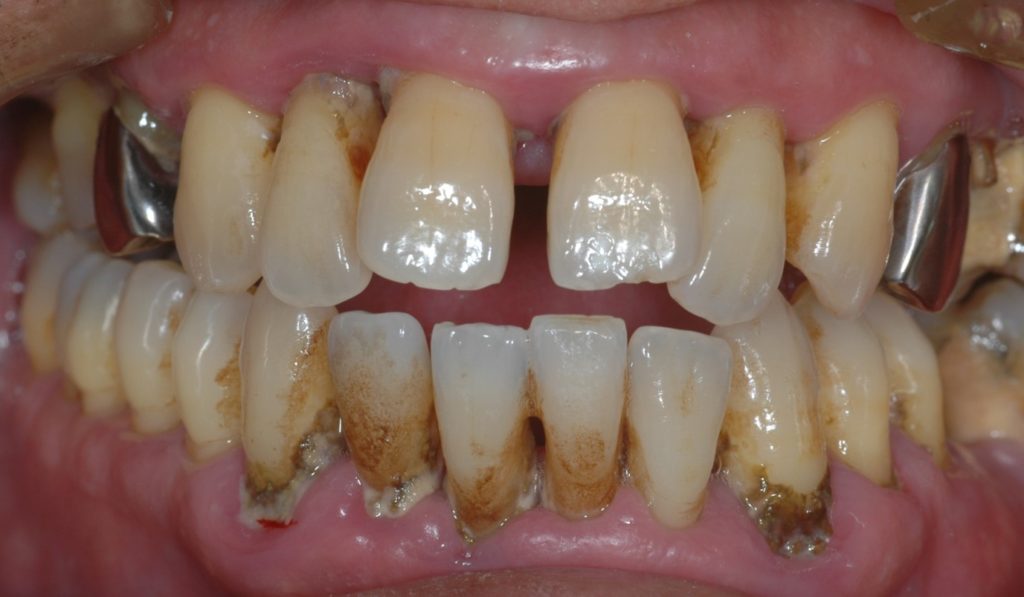

重度の歯周病(歯周炎)のケースです。

まずは初診の写真です。前歯が離れて(正中離開)、歯石(歯ぐきの中の黒い歯石)が目立ちます。また、プラークが多く付着しています。